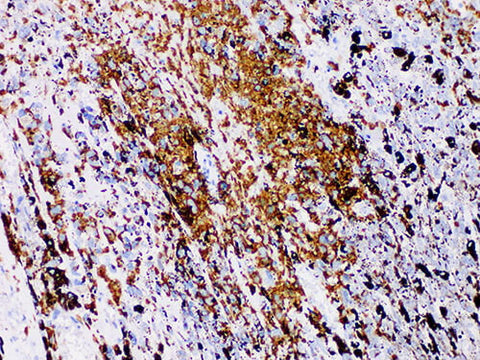

S100P Monoclonal Antibody Stored at 2~8°C

Applications IHC-P

Tissue Specificity Melanoma

S100P is a member of S100 protein family. Its abnormal expression in tumor plays an important role in tumor growth, proliferation, invasion and metastasis through various signaling pathways. It is highly expressed in placenta and pancreatic ductal adenocarcinoma, but not in benign ductal and acinar glands. S100P is reported to be expressed in all infiltrating components of intraductal papillary mucinous tumors, including nerves, lymph nodes, and microinfiltrates. S100P is strongly positive in 90% of primary cancer bile duct biopsies, but negative in benign biopsies. Therefore, S100P can help us distinguish cancer from reactive epithelial changes in bile duct biopsies. At the same time, S100P is one of the specific markers of urothelial carcinoma.